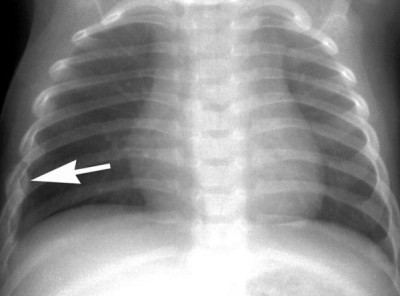

• Röntgenonderzoek.

• Beeldvormende diagnosetechnieken zoals CT-scans (computertomografie) of MRI (magnetische resonantie) worden toegepast om tumoren en gebieden met metastasen op te sporen.